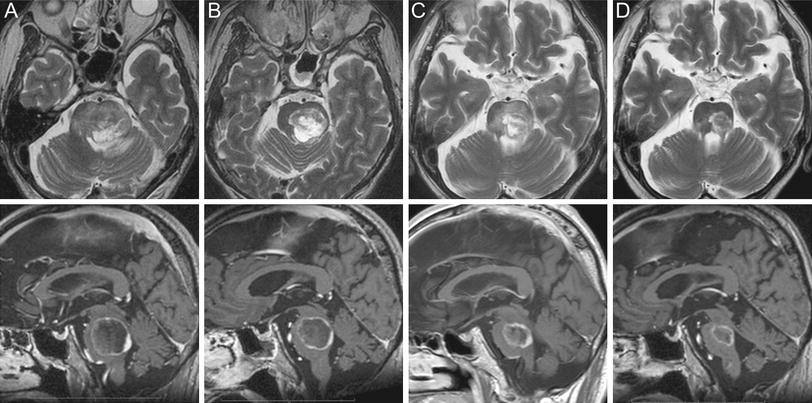

A brain tumor occurs when abnormal cells form within the brain. Are there any other risks? After a tiny hole is drilled into the skull, a small needle is placed into the.

Michael brisman, a neurosurgeon with nspc brain & spine surgery on long island, ny. Don't assume you have a brain tumor just because you have some of the your doctor will consider several things in deciding how to treat your brain tumor, including Although a brain tumor rarely causes headaches, someone with no history of headaches who develops them should be seen by a doctor. Brain tumors can affect brain function if they grow large enough to press on surrounding nerves how is a brain tumor diagnosed?